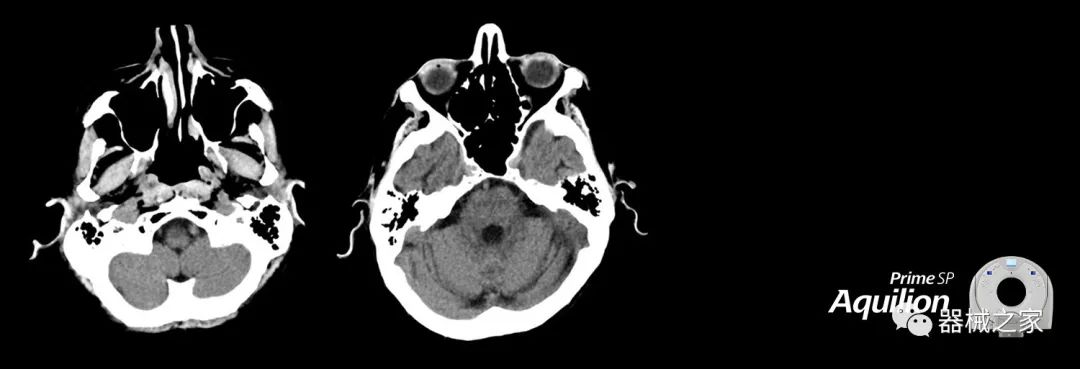

Aquilion Prime SP使設(shè)施能夠處理具有挑戰(zhàn)性的案例,同時為員工提供快速,靈活和高效的解決方案。

兩個CT系統(tǒng)均采用0.5 mm x 80排PUREViSION探測器技術(shù)(可配置并從80-160現(xiàn)場升級),78 cm孔徑,50 cm視野,AIDR(自適應(yīng)迭代劑量減少)3-D和SEMAR(單個)能量金屬神器減少)技術(shù)。